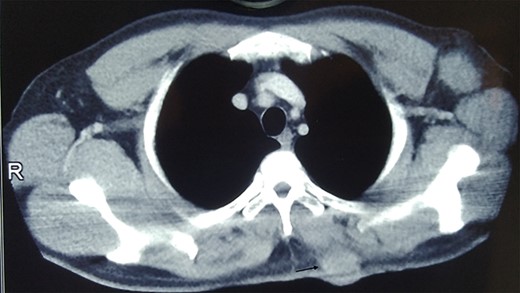

A 35-year-old male presented with large fungating lesion over his back. It was 8-cm round ulcero-proliferating lesion medial to left scapular region near spine (Fig. 1). On examination there were palpable left axillary lymph nodes. He had a history of small swelling over the same region, which was excised by local practitioner 2 months back. The details of the procedure and histopathology were not available. He is non-smoker, non-alcoholic with no history of malignancy in family. Tissue biopsy from lesion and fine needle aspiration cytology (FNAC) of left axillary lymph node side was positive for carcinoma. Contrast enhanced computed tomogram (CECT) of chest and abdomen was done. CECT showed well-defined lesion in skin and subcutaneous layer medial to left scapular region near spine (Fig. 2). There was no evidence of malignancy or metastasis to other organs in chest and abdomen. Colonoscopy, upper gastrointestinal endoscopy, CT head and ultrasound of bilateral breast was normal. FNAC of subcentric right axillary lymph node was also positive for metastasis. Therefore the diagnosis of malignant cutaneous adnexal tumor with bilateral axillary metastasis was made. He underwent wide local excision of the lesion with 2-cm margin and modified rhomboid flap coverage along with bilateral axillary dissection. Histopathology of the lesion confirmed the malignant adnexal tumor with closest resemblance to sebaceous carcinoma (Fig. 3). The margins were free of tumor cells. On immunohistochemistry examination, the tumor was positive for Her-2, GATA-3, CK-7 and EMA. It was negative for S-100, CEA, ER, PR, AR, TTF-1 PAX-8, CDX-2 and CK-20. He received radiotherapy for locoregional control. Six months later, he again presented with severe back ache. Magnetic resonance imaging was suggestive of bone metastasis. Medical oncological consultation was sought and received six cycles of Docetaxel and Cisplatin based chemotherapy. After 3 months of follow-up he is asymptomatic.

CT image showing well defined lesion in skin and subcutaneous tissue (arrow).